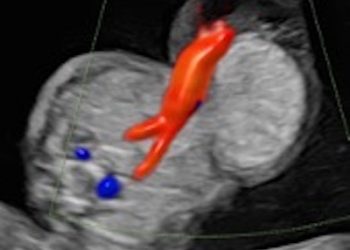

Cari soci, finalmente online le soluzioni dei casi del mese di Giugno!!! Grazie a Valentina D'Ambrosio e Alba Piras!! Caso...